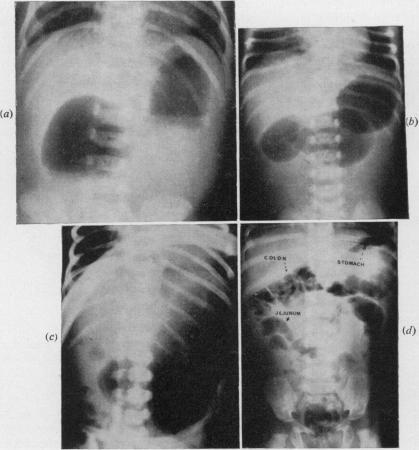

Duodenal atresia in the newborn.